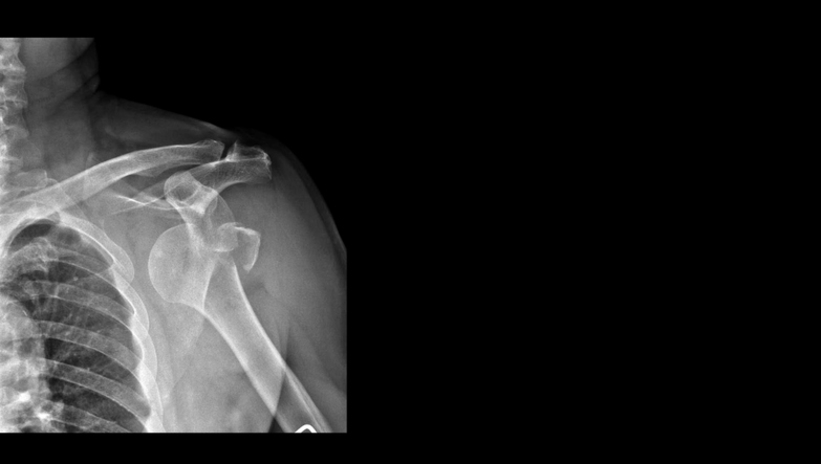

Omuz çıkıkları ortopedik aciller arasında yer alıyor. Ortopedi ve Travmatoloji Uzmanı Dr. Öğr. Ü. Burak Çağrı Aksu, düşme, sportif aktivite sırasında travma ya da epilepsi nöbeti gibi bilinç kaybına neden olan hastalıklar nedeniyle her yaş grubunda omuz çıkığı yaşanabileceğini söyledi. Omuz çıkığının, öncelikle çıkan eklemin yerine oturtulması ve sonrasında da mutlaka tıbbi tedavi altına alınması gerektiğini anlatan Dr. Öğr. Ü. Aksu, aksi durumda çıkığın tekrarlayabildiğini söyledi.

"Omuz çıkığı ortaya çıktığı zaman hasta ivedilikle acil servislere başvurur. Hastalar, omuzun iki tarafını karşılaştırıldığında simetrisinde ciddi bir değişiklik olduğunu ve eklemin yerinde olmadığını fark eder. Ayrıca kolunu hareket ettirmekte zorlanır. Omuz çıkığında ilk tedavi omuz ekleminin yerine oturtulmasıdır. Bunu genellikle acil şartlarında anestezi vermeden belki biraz rahatlatıcı bir ilaç vererek yapabiliriz."